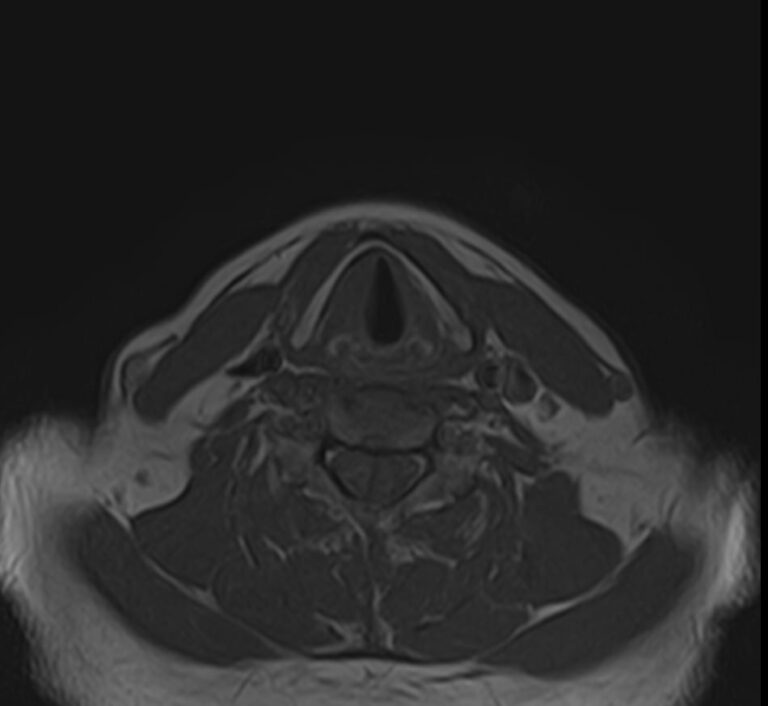

Магнитно-резонансная томография шеи предусматривает детальную визуализацию различных анатомических структур области шеи. Сюда входит полость рта, язык и корень языка, пищевод, гортань, окологлоточные лимфоузлы, шейные лимфоузлы, слюнные железы, щитовидная железа, мышцы и межфасциальные пространства.

В нашей клинике данное обследование выполняется на новейшем 32-канальном высокопольном томографе закрытого типа TOSHIBA VANTAGE TITAN 1,5 Тесла. Высокотехнологичный аппарат производит сканирование путем тончайших срезов с шагом от 1 мм в трех различных плоскостях. Используя современные компьютерные программы, полученные данные преобразуются в 3D-изображение исследуемой зоны. Это обеспечивает точность и достоверность диагностики заболеваний анатомических структур, расположенных в области шеи.

- Врожденные аномалии строения;

- Воспалительные процессы;

- Остеохондроз шейного отдела позвоночника;

- Защемление нервных окончаний;

- Наличие новообразований;

- Сужение или закупорку сосудов;

- Атрофию или повреждение мышц;

- Абсцессы;

- Наличие аневризм;

- Поражения лимфатических узлов.